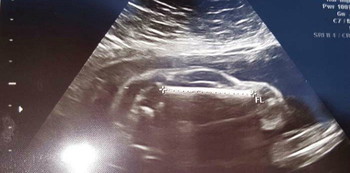

Mashable first broke the unusual, albeit hilarious, story of Reddit user Brewhaus3223 and his wife. Apparently, the couple visited their doctor for a routine 24-week ultrasound. Much to their surprise, instead of seeing their child on the screen, they saw this:

Source: Reddit

If you’re having trouble making out the image…it’s a car! Now, before we make any strange theories, you should know that this mother will not actually be birthing a car on her due date. For some unexplained reason, that’s just what the ultrasound reading appeared as. Call it an optical illusion, call it a err on the part of the machine–any excuse will work.

The couple has remained lighthearted about the outcome of the ultrasound. They shared the image on Reddit with the following caption: “A miracle happened and my wife became pregnant naturally, well as naturally as you can when you’re carrying a car. It’s a boy car!”